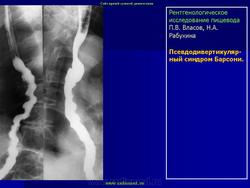

Синдром. Барсони синдром. +

Барсони синдром.